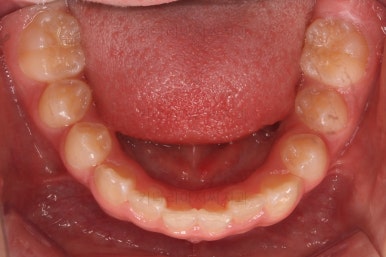

초진 시 입안의 모습입니다.

전반적으로 치열이 삐뚤삐뚤하고요.

그리고 전반적으로 아래 치열이 윗니에 비해 뒤로 밀려 있어서, 어금니의 맞물림이 좋지 못하고 듬성듬성해 보이는 상황이었어요.